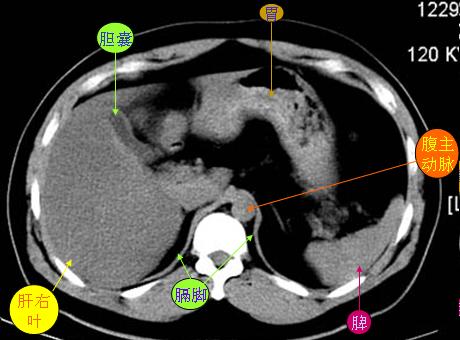

腹部ct解剖与基本病变